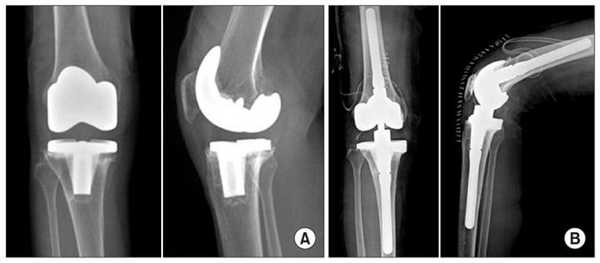

Если сустав поражен указанным на изображении образом, то возможна его частичная замена.

Основной метод лечения - постановка эндопротеза вместо поврежденного сустава. Раньше выполнялось преимущественно тотальное эндопротезирование коленного сустава, однако сейчас активно развивается другое направление - одномыщелковое (частичное) эндопротезирование.

Имплант на рентгене.

Сравнение двух типов операций.